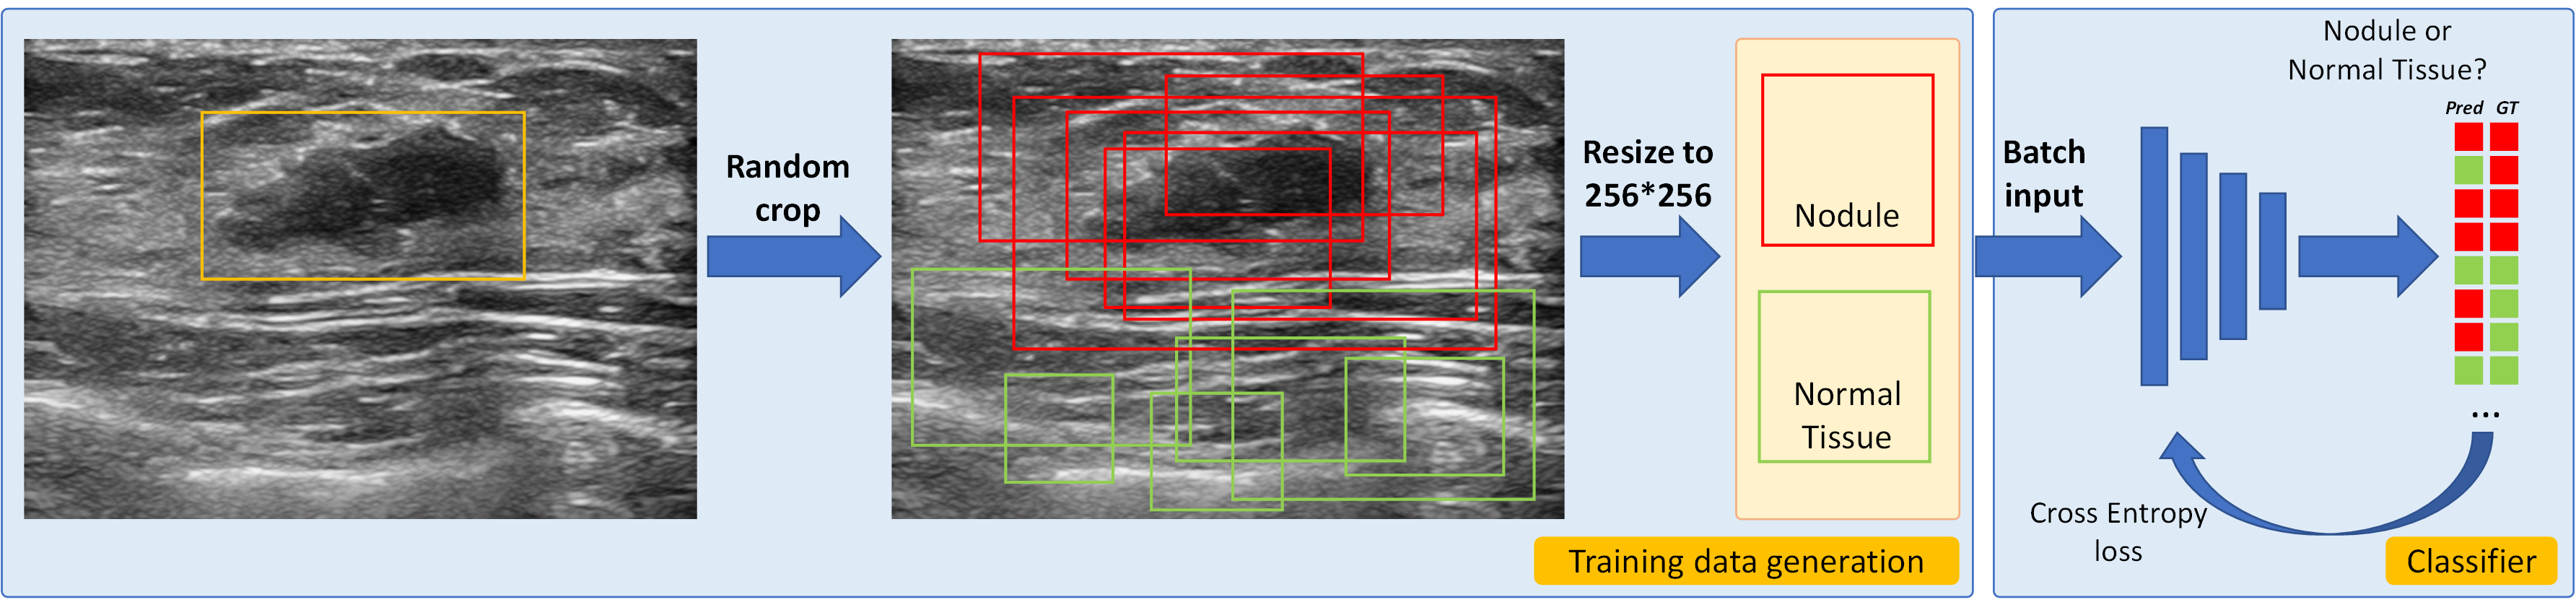

3.1 Pseudo Samples Generation for Classifier Construction

In our study, developing a classifier for distinguishing between nodule and normal tissue is pivotal, serving two main purposes: 1) selecting the eraser source and 2) providing flip signals. For more details, please refer to Sections 3.2 and 3.3.

As we only have nodule images from both BUS and ABUS datasets and lack samples from healthy individuals, it is necessary to generate normal samples to facilitate the training of the binary classification network. To address this, we propose utilizing the self-information of the weak nodule annotation (2D/3D box) to generate adequate normal/abnormal breast data. In Figure 4, we extract patches (green boxes) randomly that do not overlap with the nodule annotation (yellow box) to serve as negative data (tag: normal tissue). Furthermore, randomly selected boxes that cover more than 50%50\% of the nodule area (red boxes) are identified as positive data (tag: nodule) to enhance the diversity of the nodule dataset. These generated samples can then be used to train the classification network.

Fig. 4: Introduction to the pre-trained classifier.